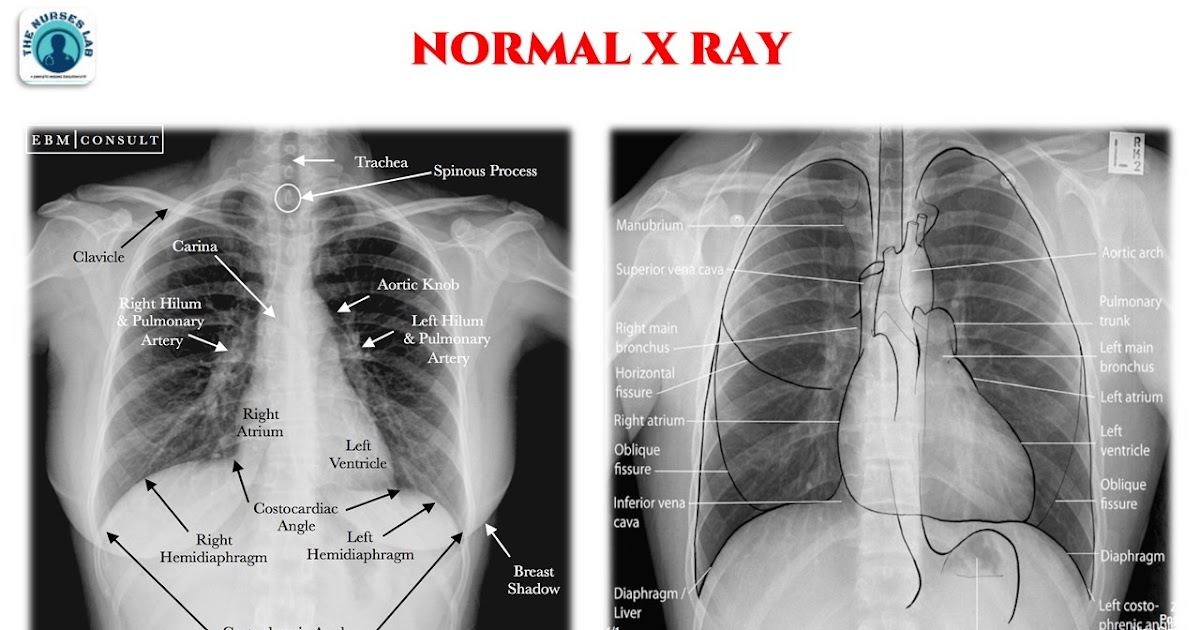

Normal Chest X Ray Image With Labels at Andrew Lee blog

From www.ebmconsult.com

Radiology Chest Xray Normal Chest X Ray Labeling Quiz Which finding is present on this image? There is a printable worksheet available for. 159 rows litfl 100 (150) cxr quiz. There are 52 questions available in this quiz. study with quizlet and memorize flashcards containing terms like lung apices (apex), right costophrenic angle, left costophrenic angle and. Chest X Ray Labeling Quiz.